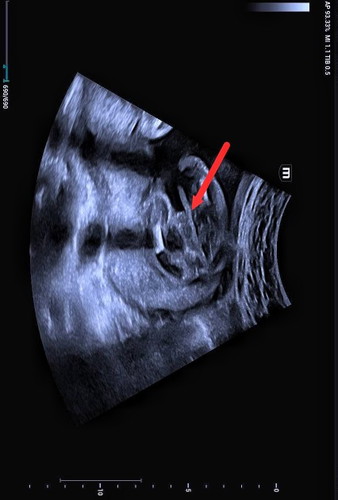

ลูกเพศอะไร??ตรงลูกศรที่ชี้👶💗

แม่ๆช่วยดูหน่อยค่ะว่าน้องเป็นเพศอะไรหญิงหรือชายคุณหมอยังไม่คอนเฟิร์ม 100% ค่ะ แม่ตื่นเต้นค่ะ😂😁